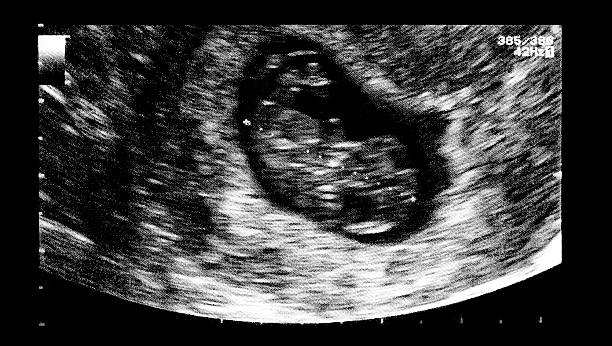

子宮腺肌病是一種常見(jiàn)的婦科疾病,其主要特征為子宮內(nèi)膜組織侵入到子宮肌肉層并引發(fā)相關(guān)癥狀。對(duì)于患有該疾病的女性來(lái)說(shuō),懷孕可能會(huì)面臨一定挑戰(zhàn)。而隨著輔助生殖技術(shù)的發(fā)...

子宮腺肌癥是一種常見(jiàn)的婦科疾病,主要表現(xiàn)為月經(jīng)量增多、經(jīng)期延長(zhǎng)以及痛經(jīng)等癥狀。對(duì)于患有此病的女性來(lái)說(shuō),在備孕過(guò)程中可能會(huì)面臨更多挑戰(zhàn)。那么,當(dāng)面對(duì)這種情況時(shí),是...

子宮腺肌病是一種常見(jiàn)的婦科疾病,主要表現(xiàn)為子宮內(nèi)膜組織侵入到子宮肌肉層生長(zhǎng),導(dǎo)致患者出現(xiàn)月經(jīng)量過(guò)多、痛經(jīng)以及不孕等癥狀。對(duì)于患有此疾病的女性來(lái)說(shuō),生育問(wèn)題往往成...

子宮腺肌病是一種常見(jiàn)的婦科疾病,主要表現(xiàn)為子宮內(nèi)膜組織異常侵入到子宮肌肉層,從而引發(fā)一系列癥狀,如月經(jīng)不調(diào)、痛經(jīng)以及不孕等。對(duì)于患有該疾病的女性來(lái)說(shuō),生育問(wèn)題常...